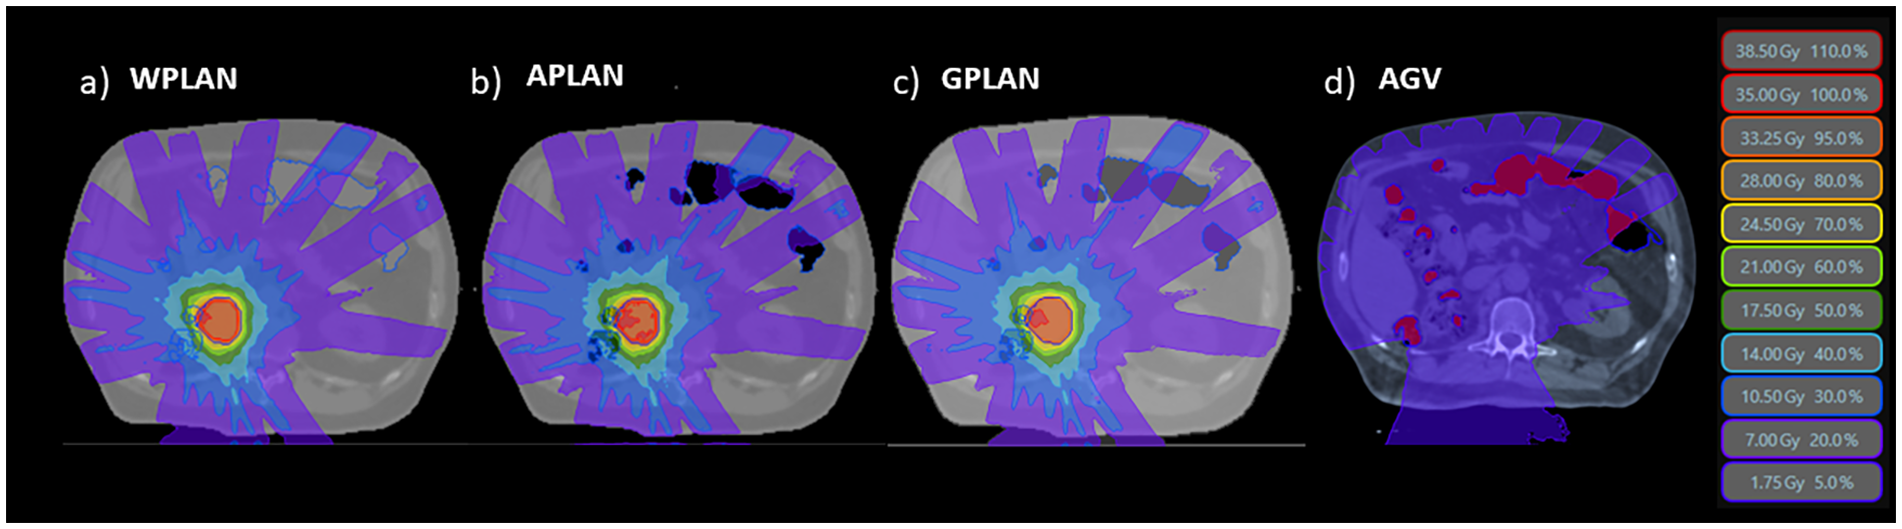

generating respectively the APLAN, WPLAN and the GPLAN. WPLAN aims to simulate the extreme-case scenario of the patient presenting completely without air pockets. All clinical initial plans were calculated using the MRIdian (ViewRay Technologies Inc., Oakwood Village, OH) TPS by an experienced medical physicist. The planning was realized using the MRIdian Planning Technique (MPT) (17, 18) a particular technique for robust online adaptive planning. The plans were optimized using a standard template for the positioning and number of the Linac gantry angles. Twenty-four beams were equally distributed around the patient, except for two small sectors of about 20 degrees positioned at about 120 and 240 degrees where no radiation beams were present to avoid couch edges. All treatment plans dose prescriptions were at the 80% isodose and ranged from 35 to 40 Gy. Dose optimization for IMRT step-and-shoot treatments was then performed using the Kawrakow Monte Carlo (KMC) algorithm (19) on the MRIdian TPS (2500000 histories, dose grid 1.0 x 1.0 mm2, 1% of recalculation uncertainty (20)). 2-D dose distributions obtained for APLAN, WPLAN and GPLAN were compared to each other in terms of gamma analysis (1%/1mm, threshold 10%) (21, 22).. The thresholds of the gamma analysis were chosen to be as tight as possible, being the calculation grid of both dose distributions of 1 mm and the recalculation error of the TPS being estimated at 1%. 2-D gamma analysis was performed separately for the three projections of dose on the three orthogonal planes passing through the centroid of the GTV. Mean value of the three relative gamma passing rates was then considered to evaluate differences in dose distribution. In addition, a parameter called active gas volume (AGV) was introduced and calculated as the intersection of the GAS structure with the isodose of 5% of prescription dose (Figure 2). AGV aims to evaluate and quantify the volume of gas invested by beam path. The Pearson correlation index was computed to verify the correlation between GPR values and the AGV parameter. Finally, DVH analysis was performed extracting the following values to assess dose distribution variation: the percentage volume of PTV covered by 95% of the prescription dose (PTV_V95), minimum dose to PTV as the isodose level that covers the 98% of the PTV volume (PTV_D98), the mean dose to PTV (PTV_D50) and the maximum dose to PTV as the isodose level that covers the 2% of the PTV volume (PTV_D2). Minimum, mean and maximum dose values were then extracted from DVH for the three GIOARs as done for the PTV. The differences of these extracted values for each plan comparison were computed and analyzed.

Figure 2

The three different dose distributions due to the recalculation of the treatment plan on the different electronic density maps generated by overwriting the volume of gas pockets with RED of water (A - WPLAN), RED of air (B - APLAN) and GIGED (C - GPLAN). In D we show the 5% prescription dose isodose intersecting the AIR structure defining the AGV parameter.